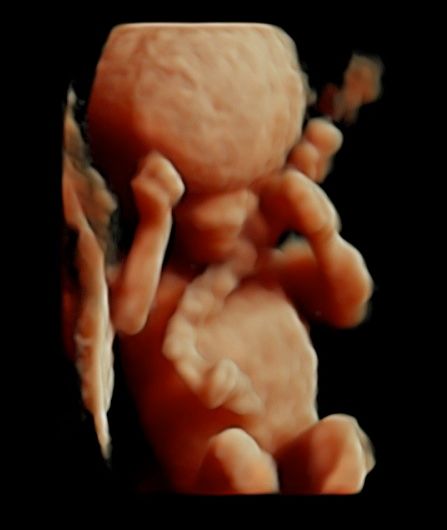

Subito dopo la laurea, il dottor Tommaso Incandela, ha conseguito l'idoneità ospedaliera nella branca di Ostetricia e Ginecologia con il giudizio finale di ottimo. Dall'Aprile 1977 fino al Gennaio 1982, su delibera del consiglio di facoltà, ha svolto la funzione di medico interno della seconda cattedra di Ostetricia e Ginecologia con mansioni didattiche, di assistenza e di cura. Dal Luglio 1981 al mese di Ottobre 1992 ha ricoperto la funzione di assistente di ruolo presso la seconda divisione di Ostetricia e Ginecologia dell'Ospedale Civico e Benfratelli di Palermo. Dal 1 Novembre 1992 fino alla fine di Giugno 1998 è stato dirigente medico del Consultorio familiare di Santa Flavia. Dal Luglio 1998 a tutt'oggi si dedica a tempo pieno all'attività libero professionale occupandosi di ecografia ostetrica e ginecologica con particolare riguardo per la diagnosi prenatale di patologie cromosomiche e malfomative (studio di aneuploidie cromosomiche su DNA fetale prelevato dal sangue materno, amniocentesi precoce, ecocardiografia fetale, ecografia morfologica e cardiotocografia) tutte queste indagini sono inserite nel monitoraggio della gravidanza. Il dottor Tommaso Incandela si occupa altresì di diagnosi precoce e terapia di patologie del tratto genitale inferiore e nel corso degli anni ha acquisito una notevolissima esperienza nell'ambito della terapia conservativa dei fibromi uterini mediante terapia farmacologica e/o inserimento di spirali medicate al progestinico. Da un punto di vista chirurgico il dottor Incandela si occupa di patologie del corpo uterino ivi compresa l'asportazione di fibromi con conservazione dell'utero stesso anche in pazienti meno giovani e con assenza di desiderio di prole. Il dottor Incandela si occupa anche di chirurgia del pavimento pelvico con particolare riguardo per la terapia dell'incontinenza urinaria, dei prolassi uterini e vescicali e delle lacerazioni antiche da parti pregressi.

Foto e video

• Ecocardiografia fetale

• Ecografia morfologica